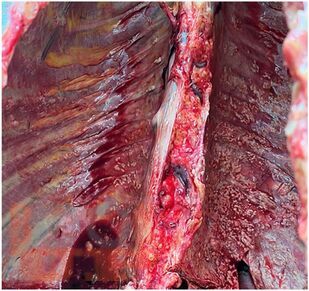

В атласе представлены авторские снимки макро- и микропрепаратов, демонстрирующих проявления канцероматозного лимфангита. В цветных иллюстрациях в описании макро- и микропрепаратов сделан акцент на наиболее важных макроскопических и гистологических изменениях, позволяющих диагностировать и дифференцировать канцероматозный лимфангит. Микропрепараты подготовлены Завьяловой М.В.